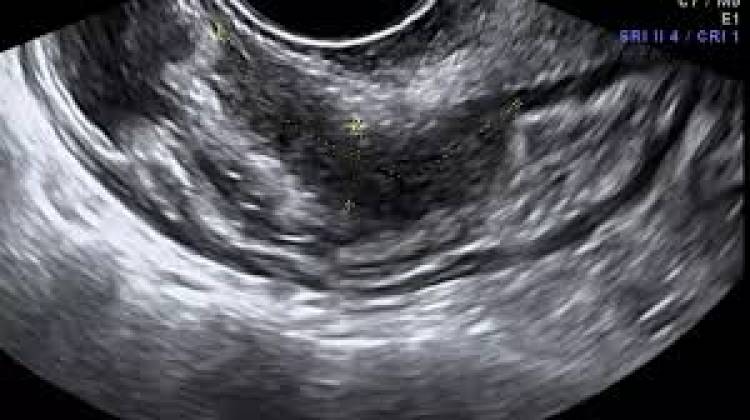

Además, la utilización de guías clínicas basadas en evidencia en el territorio de la provincia garantiza que todas las personas puedan acceder a la misma calidad de atención, más allá del lugar donde vivan. La organización clara y ordenada de los circuitos que deben seguir las personas con endometriosis dentro de la red de salud facilita el acceso oportuno, ágil y efectivo cuando se requieran procedimientos de mayor complejidad, como ecografías, resonancias y otros estudios.